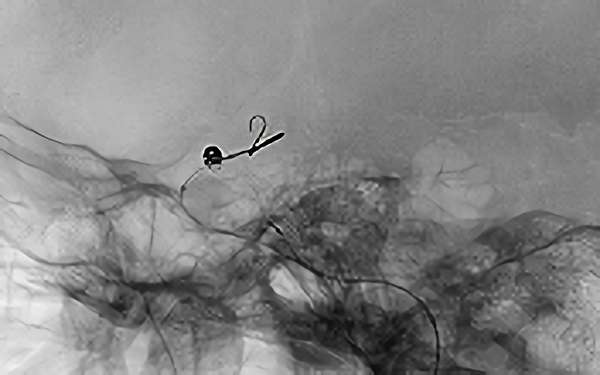

'26年4月

左内頚動脈脳動脈瘤

70代

大阪府の病院

No.1630 手術前

No.1630 手術中

No.1630 手術後